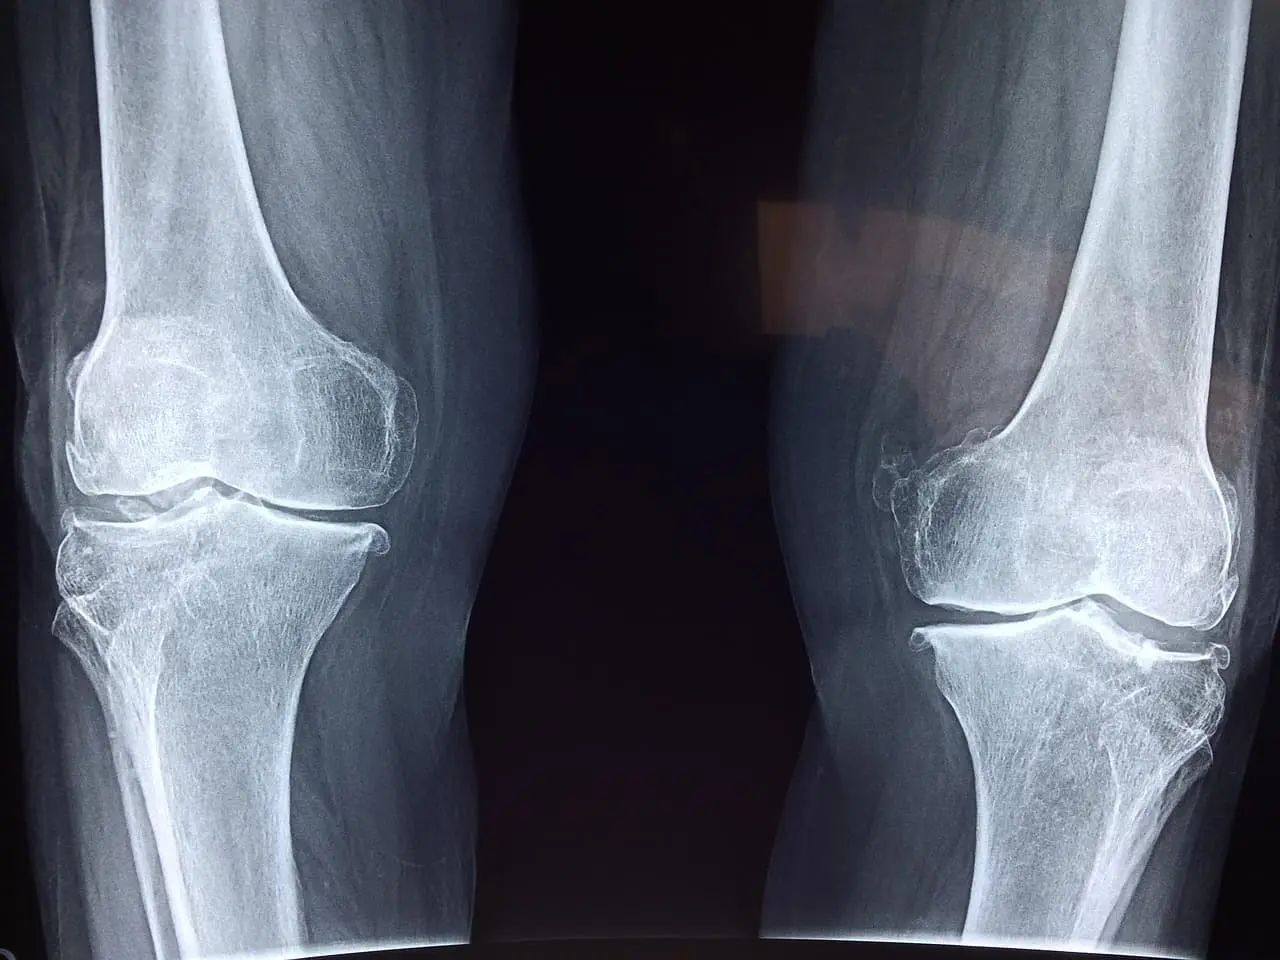

골흡수억제제 vs 골형성촉진제 – 치료 효과의 차이는?

✔ 골흡수억제제 (1차 치료제)

- 대표 약: 알렌드로네이트, 데노수맙

- 작용 기전: 뼈를 분해하는 세포(파골세포)를 억제

- 장점: 보험 적용 용이, 경구제 또는 주사제 형태 다양

- 단점: 골밀도 개선 폭이 작고, 골절 예방 효과 제한적

▶ 골밀도 개선 확률: 10% 미만

✔ 골형성촉진제 (2차 치료제)

- 대표 약: 로모소주맙, 테리파라타이드

- 작용 기전: 뼈를 생성하는 세포(조골세포)를 자극

- 장점: 골밀도 개선 속도 빠름, 골절 예방 효과 뛰어남

- 단점: 건강보험 적용 제한, 고가 (월 25~30만 원)

▶ 골밀도 개선 확률: 60% 이상

▶ 척추 골절 위험 최대 70% 감소,

▶ 비척추 골절 위험도 50% 감소

같은 골밀도 개선에도 6배 이상의 치료 효과 차이가 있다면,

지금 내 치료 선택권에 대한 의문을 가져보는 게 필요하지 않을까요?